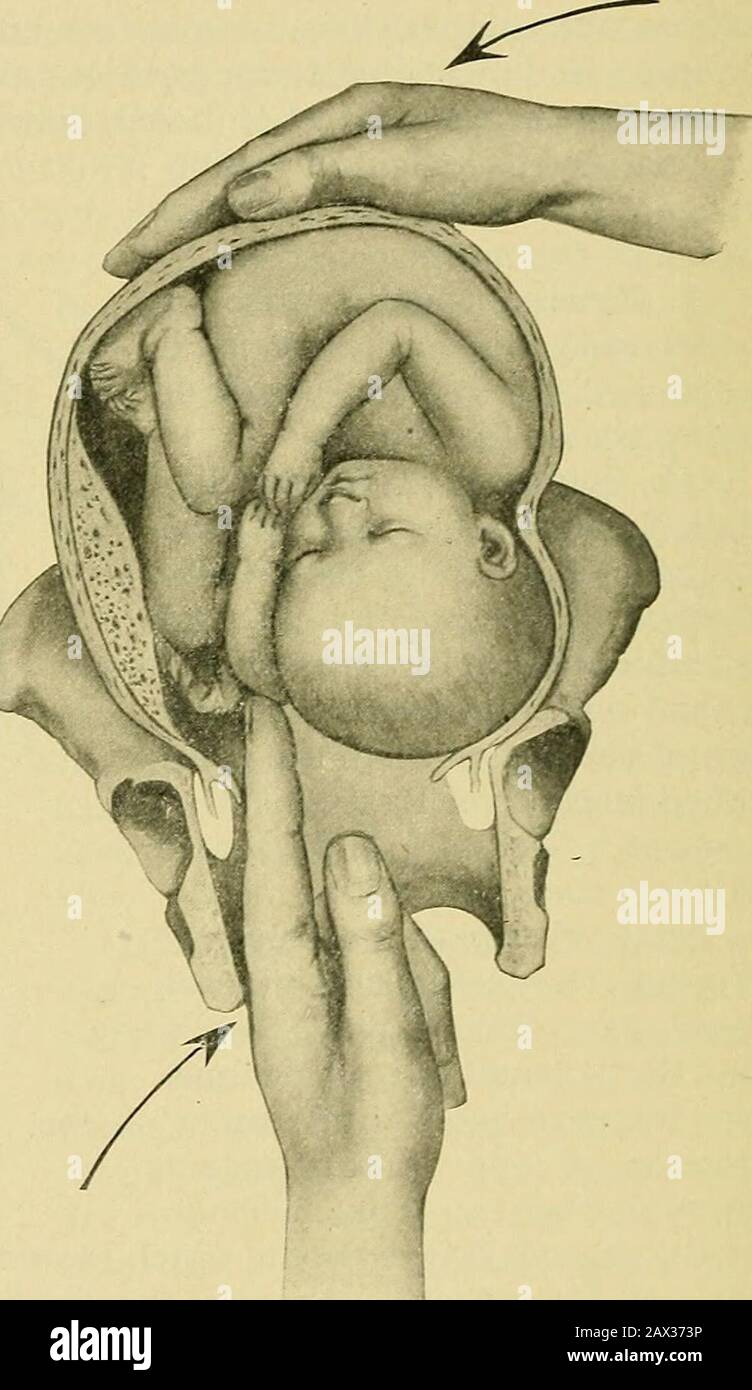

The practice of obstetrics, designed for the use of students and practitioners of medicine . t fronto-anterior and -posterior—the left hand is the one to use in-ternally for grasping the foot or feet, as this hand most naturally by the shortestpath and with least disturbance of the fetal ellipse comes to the feet and readilyselects one or both for traction. However, in right dorso positions—namely, inright occipito-anterior and -posterior, in left mento-anterior and -posterior, andin left fronto-anterior and -posterior—the righthand should be used, for the above reasons.In pelves flattened fro Stock Photohttps://www.alamy.com/image-license-details/?v=1https://www.alamy.com/the-practice-of-obstetrics-designed-for-the-use-of-students-and-practitioners-of-medicine-t-fronto-anterior-and-posteriorthe-left-hand-is-the-one-to-use-in-ternally-for-grasping-the-foot-or-feet-as-this-hand-most-naturally-by-the-shortestpath-and-with-least-disturbance-of-the-fetal-ellipse-comes-to-the-feet-and-readilyselects-one-or-both-for-traction-however-in-right-dorso-positionsnamely-inright-occipito-anterior-and-posterior-in-left-mento-anterior-and-posterior-andin-left-fronto-anterior-and-posteriorthe-righthand-should-be-used-for-the-above-reasonsin-pelves-flattened-fro-image343043188.html

The practice of obstetrics, designed for the use of students and practitioners of medicine . t fronto-anterior and -posterior—the left hand is the one to use in-ternally for grasping the foot or feet, as this hand most naturally by the shortestpath and with least disturbance of the fetal ellipse comes to the feet and readilyselects one or both for traction. However, in right dorso positions—namely, inright occipito-anterior and -posterior, in left mento-anterior and -posterior, andin left fronto-anterior and -posterior—the righthand should be used, for the above reasons.In pelves flattened fro Stock Photohttps://www.alamy.com/image-license-details/?v=1https://www.alamy.com/the-practice-of-obstetrics-designed-for-the-use-of-students-and-practitioners-of-medicine-t-fronto-anterior-and-posteriorthe-left-hand-is-the-one-to-use-in-ternally-for-grasping-the-foot-or-feet-as-this-hand-most-naturally-by-the-shortestpath-and-with-least-disturbance-of-the-fetal-ellipse-comes-to-the-feet-and-readilyselects-one-or-both-for-traction-however-in-right-dorso-positionsnamely-inright-occipito-anterior-and-posterior-in-left-mento-anterior-and-posterior-andin-left-fronto-anterior-and-posteriorthe-righthand-should-be-used-for-the-above-reasonsin-pelves-flattened-fro-image343043188.htmlRM2AX2Y2C–The practice of obstetrics, designed for the use of students and practitioners of medicine . t fronto-anterior and -posterior—the left hand is the one to use in-ternally for grasping the foot or feet, as this hand most naturally by the shortestpath and with least disturbance of the fetal ellipse comes to the feet and readilyselects one or both for traction. However, in right dorso positions—namely, inright occipito-anterior and -posterior, in left mento-anterior and -posterior, andin left fronto-anterior and -posterior—the righthand should be used, for the above reasons.In pelves flattened fro